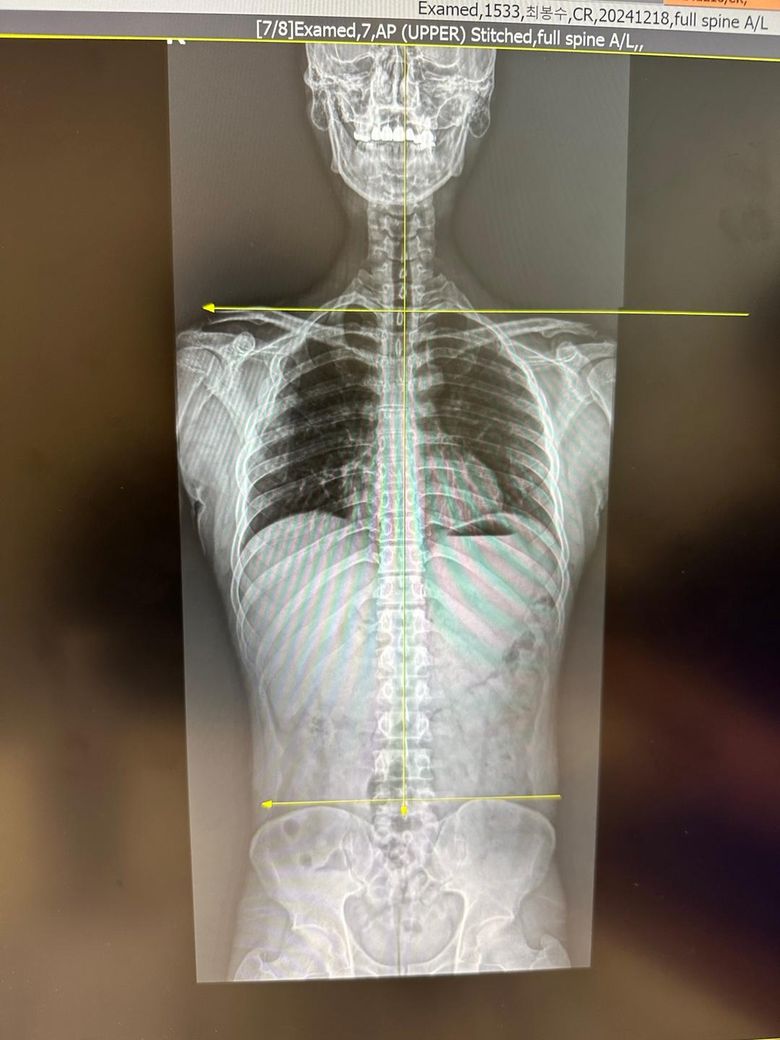

양쪽 어깨가 맞춰지는 곳 공간이 달라요..

엑스레이 찍어봤는데, 양쪽 어깨가 끼워맞춰지는 곳이 다르게 보이고...

한눈에 봐도 한쪽 어깨가 올라가고, 짧아져 있다는게 보입니다...

아무튼 약간의 골반 비대칭과 양어깨의 쇄골이 어깨로 이어지는 부분의 공간이 달라 어깨도 살짝 비대칭이신것 같은데요.

지금 보여주시는 엑스선 사진만보고 추론하건데 상당히 밸런스가 잘잡힌 좌우 형태를 가지신분이라 단언할만큼이요.